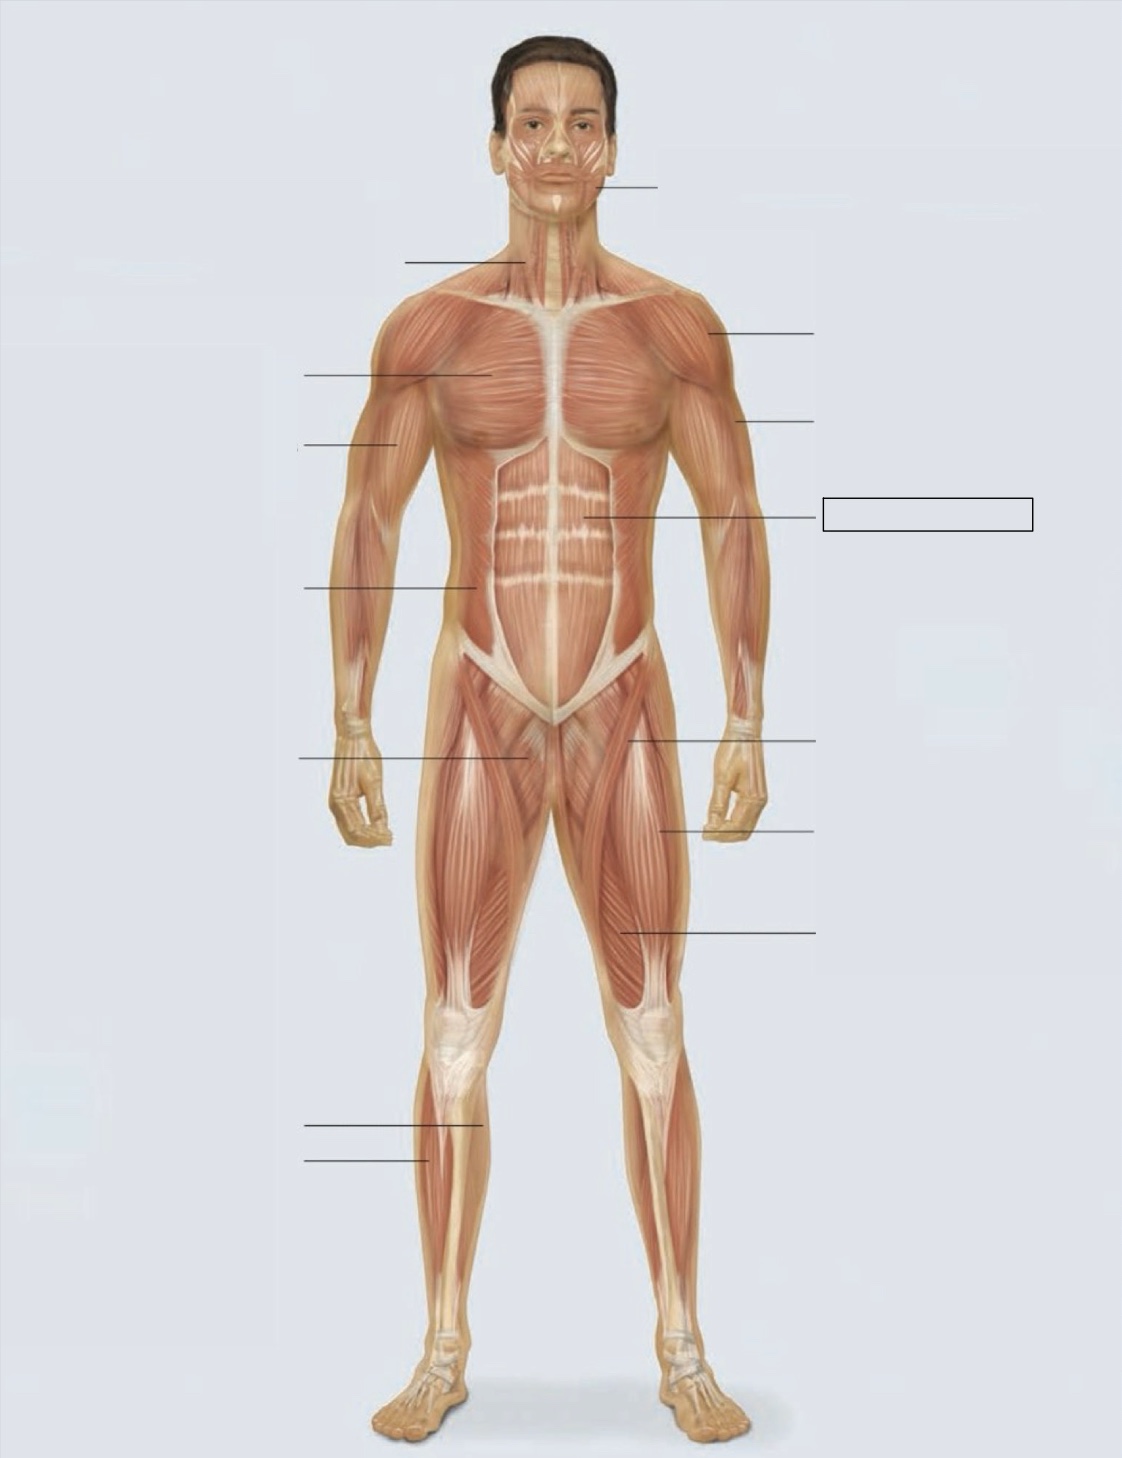

masseter

deltoid

triceps

rectus abdominis

sartorius

quadriceps femoris